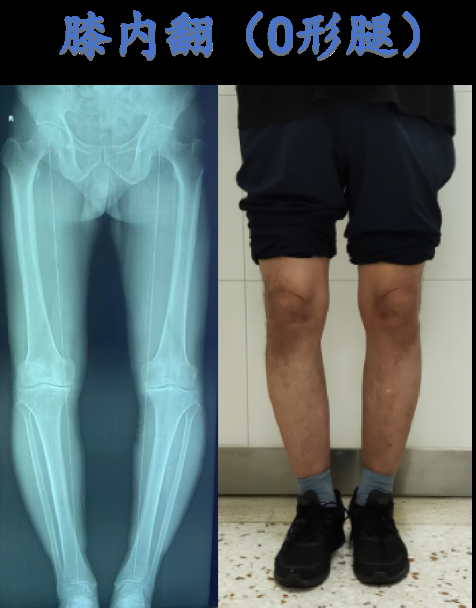

1、1先天性因素部分人因先天膝盖骨结构异常如髌骨发育异常,导致骨骼形态突出2过度使用长期跑步跳跃或下蹲等重复性动作,可能引发膝盖周围肌肉韧带劳损,间接导致骨骼突出3创伤骨折脱位或半月板损伤等外伤,可能改变膝盖骨位置,引发形态异常4疾病影响骨关节炎类风湿性关节炎;膝盖外侧骨头突出可能有几个原因1生理性,有些人因为先天发育不良可能会导致膝关节轻度外翻,也就是O型腿,是属于生理现象,一般无症状,无需治疗2外伤,若膝关节遭受外力击打或碰撞可能会导致膝关节的骨头发生骨折,骨折端移位较严重,从而导致膝关节外侧骨头突出,同时会伴有肿胀活动受限,需;膝盖骨突出尖尖的骨头,建议采取以下措施就医面诊首先,应尽快前往医院,找专业医生进行面诊医生会结合查体初步判断突出的原因完善检查在医生的指导下,完善膝关节的X线检查,以判断是否存在明显的骨质增生骨刺,或者骨软骨瘤骨肉瘤等问题针对治疗骨质增生骨刺若诊断为骨质增生或骨刺;可能病因髌下韧带增生这是导致膝盖外侧下面骨头突出的一个常见原因髌下韧带连接着髌骨和胫骨,如果发生增生,可能会使得该区域显得突出纤维瘤纤维瘤是另一种可能导致膝盖外侧下面骨头突出的原因纤维瘤通常是良性的,但也需要通过专业检查来确认就医建议前往医院外科部门为了准确判断病因。

2、膝盖上出现骨头突出的情况确实需要引起重视这种症状可能是由于骨刺或关节鼠引起的骨刺通常是由于长期的磨损或炎症导致骨头边缘增生,而关节鼠则是关节囊或滑膜增厚的结果无论是哪一种情况,都可能对日常生活造成影响,尤其是行走和站立时可能会感到疼痛或不适骨刺或关节鼠的形成往往与年龄增长过度;膝盖摔伤以后有骨头凸起,如果凸起的面积比较大,可能是关节脱位造成的如果局部突出比较明显,而且凸起的面积比较小,可能是因为髌骨骨折并且移位引起的,也有可能是由于局部血肿形成的所以当膝盖摔伤以后有骨头凸起,首先患肢免负重,避免剧烈活动,卧床休息,抬高患肢,给予膝关节支具外固定,限制关节的;儿童膝盖内侧骨头突出可能有以下几种原因骨骼肿瘤骨软骨瘤骨囊肿骨肉瘤等可能导致局部骨头突出这类疾病通常会伴有局部疼痛或不适,且可以用手扪及明显的硬包块骨骼发育畸形如存在膝外翻,膝关节总体外形会有明显异常,表现为膝盖内侧骨头突出膝关节外伤骨折骨折后局部畸形愈合或生长的骨痂;若发现膝盖突出一块骨头,应及时就医检查,明确原因后采取针对性治疗措施,具体如下就医检查若膝盖突出处伴有疼痛肿胀活动受限或影响日常生活,需尽快就诊医生会通过体格检查如触诊关节活动度测试结合影像学检查如X光CTMRI明确病因影像学可清晰显示骨骼结构软骨状态及软组织情况;膝盖下面的骨头突出很高,是指胫骨的胫骨粗隆,这是一个正常的生理结构,本身就是一个比较突出明显的骨性结构,不需要进行特殊的处理另外,也有可能是在青少年时期,胫骨粗隆的位置受过外伤导致骺软骨出现损伤,影响正常的发育,也有可能会导致局部形成肿胀畸形的情况,也会表现为这个地方骨头比另一侧明显;1 腓骨小头是膝盖外侧的一个正常骨性突起,天生较其他区域更突出2 体瘦的人可能因为这个原因,使得这个骨性突起更加明显3 考虑到外生软骨瘤的可能性,应当进行相应的排除检查4 若日常生活中未感到不适,可能无需特别治疗,但若有必要,进行X线检查以排除软骨瘤5 如果确诊为软骨瘤,治疗。

3、小孩子一侧膝盖内侧骨头突出,可能是局部骨骼的发育畸形膝外翻,也可能是局部的地方骨骼肿瘤病变,比如骨软骨瘤,可以完善膝关节X片检查初步判断病情,必要时结合CT及三维重建如果是骨骼发育畸形,不影响膝关节正常力线可以随访观察,如果明显膝外翻导致内侧凸起,而且影响膝关节力线,可以手术截骨矫形如;孩子膝盖侧面骨头突出可能是局部发育的问题,比如先天性的膝关节内外翻畸形,这种情况左右都是凸起,而且相对比较对称,除外观凸起没有明显的疼痛等症状另外,也可能是局部骨骼肿瘤病变,比如骨软骨瘤等,这种情况为局部局限性骨性突出,有时候伴随轻微疼痛不适,按压可以扪及较为明显的骨性包块其它的比如;膝盖下面骨头突出很高,主要是因为那是胫骨的胫骨粗隆,这是一个正常的生理结构以下是详细解释正常生理结构胫骨粗隆本身就是一个比较突出明显的骨性结构,在多数人中都会存在,且不需要进行特殊的处理外伤因素在青少年时期,如果胫骨粗隆的位置受过外伤,可能会导致骺软骨损伤,进而影响正常的发育。

4、膝盖下面的骨头突出,通常是胫骨结节骺软骨炎导致的以下是关于这一现象的具体解释突出的骨头名称膝盖下面的突出骨头被称为胫骨结节病因与发育阶段韧带牵拉胫骨结节上面附着有非常强有力的韧带,即髌韧带在跑跳剧烈活动时,髌韧带会牵拉胫骨结节,产生压力发育未完成如果个体尚未完全发育;早期症状不明显在骨质增生的早期阶段,通常没有明显的疼痛表现,因此容易被忽视只有当骨头突出的症状已经非常严重时,且开始限制活动时,人们才会注意到这一问题的严重性及时治疗的重要性一旦发现膝盖骨头突出,应尽早进行治疗,以避免病情进一步发展导致更严重的后果其他可能性除了骨质增生,膝盖骨头发生肿瘤或囊肿也可能导致突出;膝盖骨头突出主要由以下几方面原因导致膝盖部位的骨质退变增生主要见于中老年人,由于膝盖部位骨质长期受到反复的挤压摩擦,导致骨质损伤以及内部软骨断裂剥脱在膝盖周围形成明显的骨赘,即骨头突出膝盖部位的骨质病变如膝盖部位的骨软骨瘤或骨肿瘤,这些病变会导致膝盖部位骨头异常突出膝盖部;膝盖边上的骨头突出,可能与局部退变慢性劳损或发育异常相关以下是具体的分析和建议局部退变和慢性劳损这种情况较为常见,尤其在劳累受凉或剧烈运动后,突出的骨头可能伴有明显的压痛建议局部休息,避免过度活动,可以给予热敷微波理疗等缓解症状如症状严重,可口服消炎镇痛类药物,或外用非。